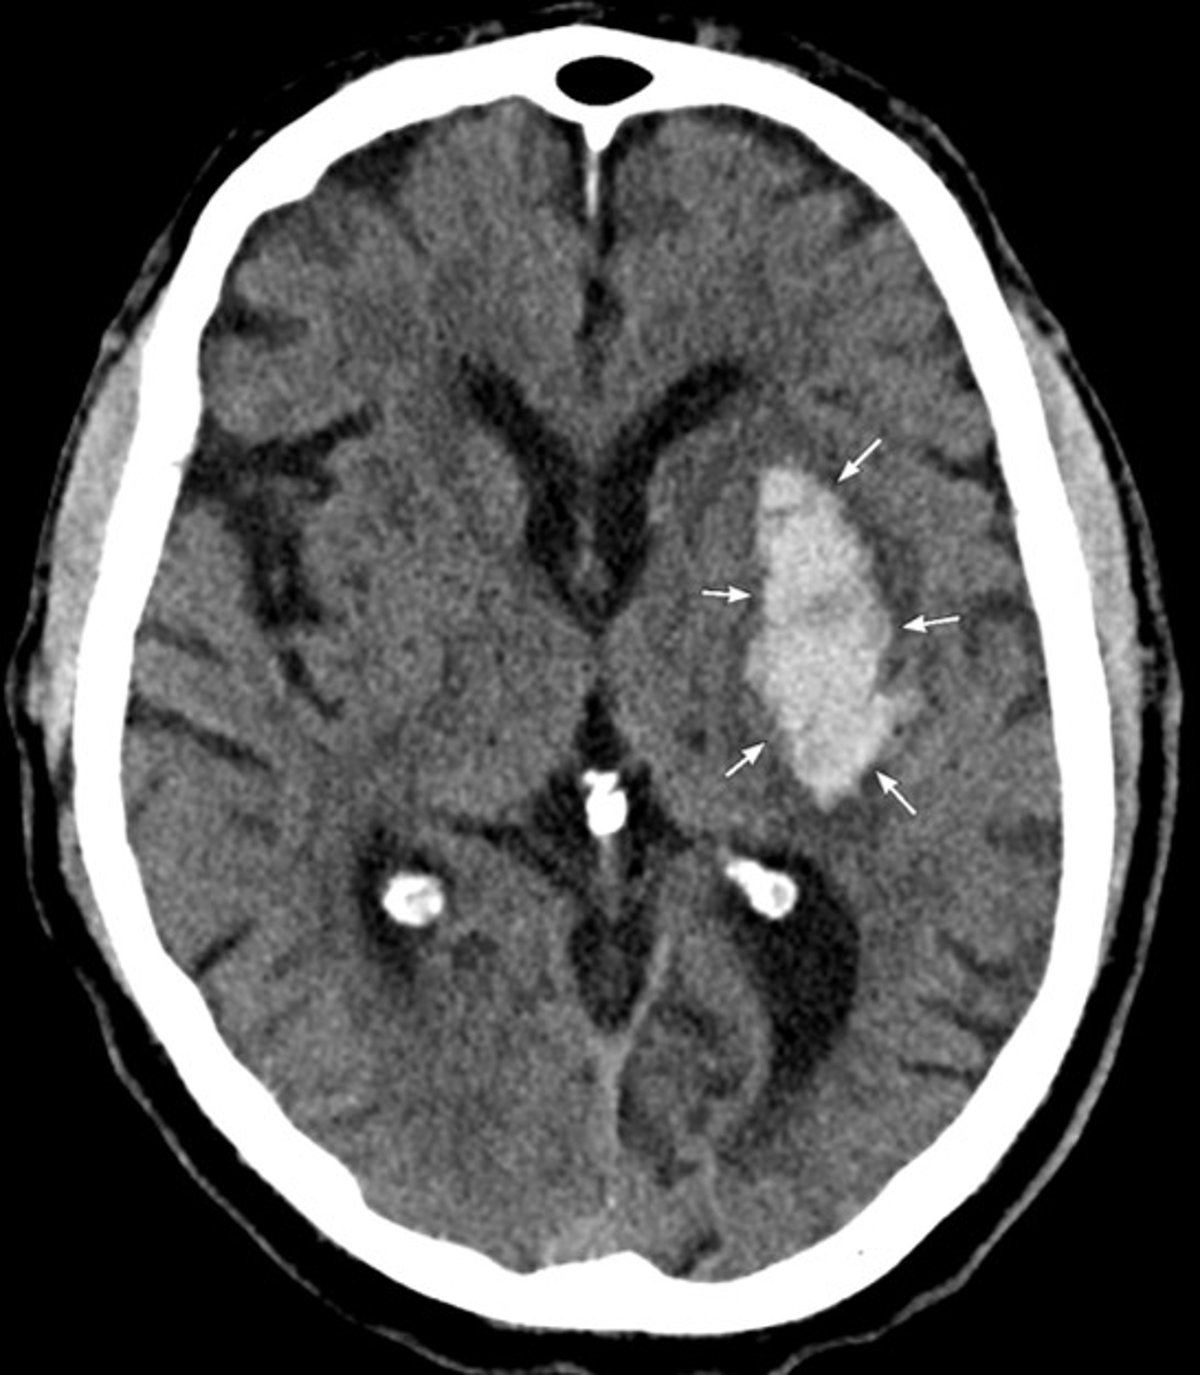

TDM de la tête

La TDM montre une hémorragie aiguë dans les noyaux gris centraux gauche compatible avec une hémorragie intracérébrale hypertensive.

Image courtoisie de Mustafa Mafraji, MD.